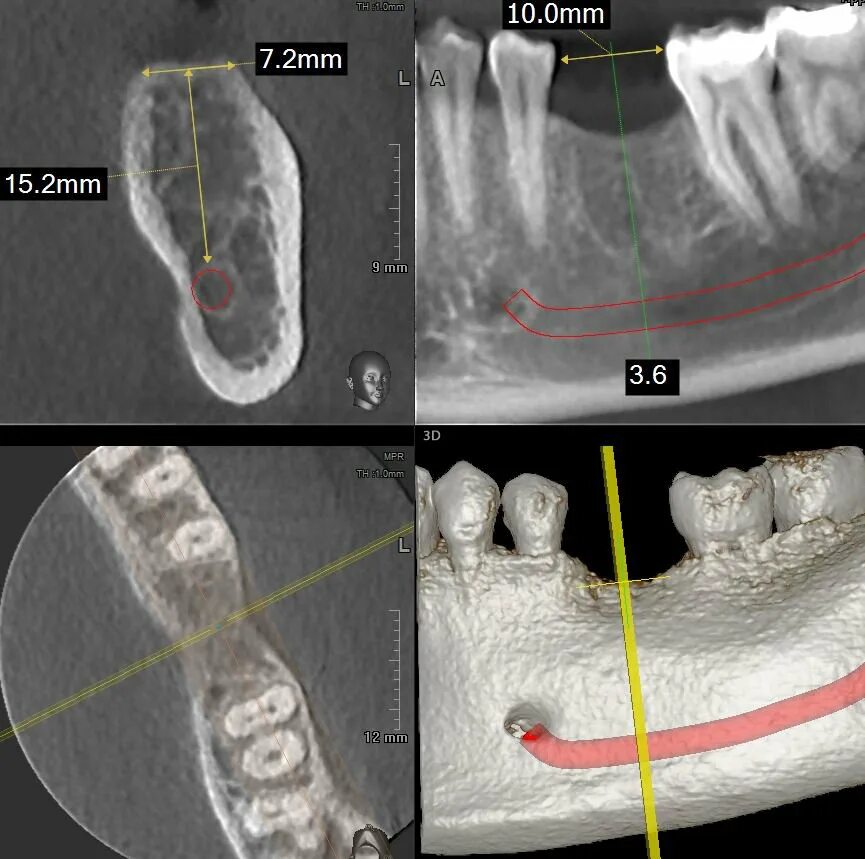

Picasso кт